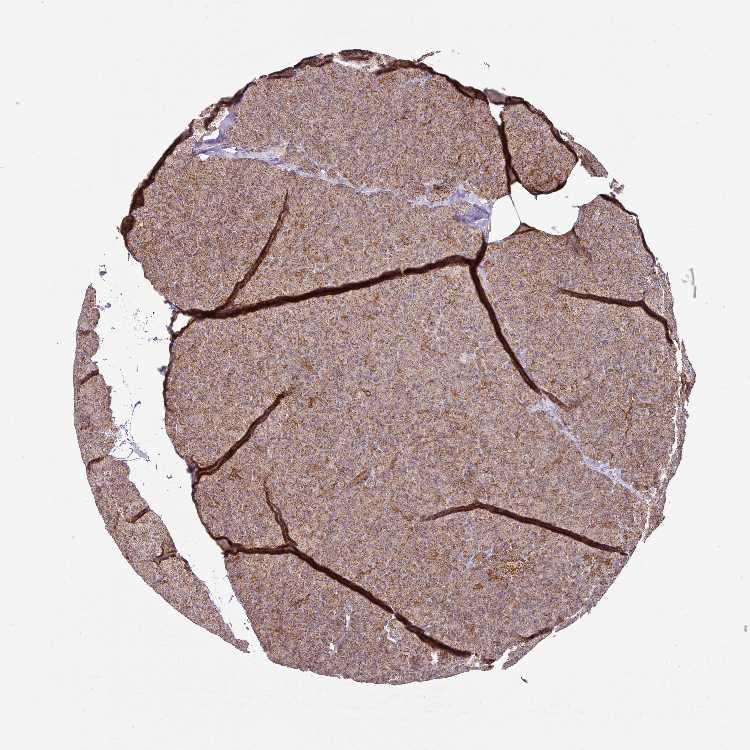

PANCREAS - Antibody stainingi

Antibody staining in the annotated cell types in the current human tissue is reported as not detected, low, medium, or high, based on conventional immunohistochemistry profiling in selected tissues. This score is based on the combination of the staining intensity and fraction of stained cells.

Each image is clickable and will lead to virtual microscopy that enables deeper exploration of all samples and also displays staining intensity scores, fraction scores and subcellular localization as well as patient and tissue information for each sample.

Antibody HPA008012Antibody HPA045506

Exocrine glandular cells MediumHigh